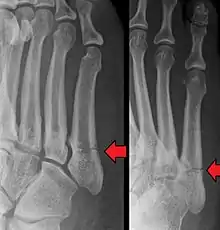

Differential diagnosis

- Proximal diaphysis, typically stress fracture.[12][13]

- Metaphysis: Jones fracture[14]

-Tuberosity: Pseudo-Jones fracture[15] (avulsion fracture).[15]

Normal anatomy:

- Apophysis: Normal at 10 - 16 years.[16]

- Os vesalianum, an accessory bone.[17]

Other proximal fifth metatarsal fractures exist, although they are not as problematic as a Jones fracture. If the fracture enters the intermetatarsal joint, it is a Jones fracture. If, however, it enters the tarsometatarsal joint, then it is likely an avulsion fracture caused by pull from the fibularis brevis tendon. An avulsion fracture at the base of the fifth metatarsal is sometimes called a "dancer's fracture" or a "pseudo Jones fracture", and usually responds readily to non-operative treatment.[18] The X-ray appearance of the developmental "apophysis" in this area may have some resemblance of a fracture, but is not a fracture; it is the secondary ossification center of the metatarsal bone. It is a normal finding that occurs at this site in adolescents.[19] If an injury to that area has occurred, the physician is often able to interpret certain radiographic clues to make the differentiation. An avulsion fracture at this location is typically extra-articular and oriented transversally as compared to the longitudinal orientation of an unfused apophysis.[19]